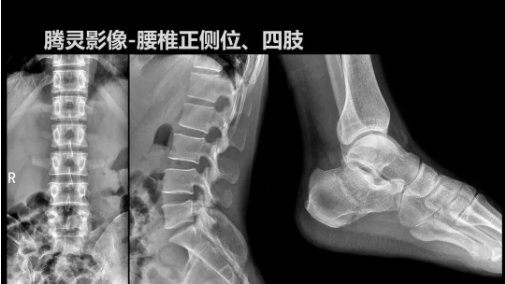

“騰靈”是安健科技的第四代動(dòng)態(tài)DR產(chǎn)品,可實(shí)現(xiàn)全科室應(yīng)用。如各類常規(guī)的X線檢查、消化道檢查、骨科檢查、婦科、兒科檢查等。此外,安健科技為“騰靈”在真正意義上實(shí)現(xiàn)多科室、多功能診斷進(jìn)行了多項(xiàng)針對性設(shè)計(jì)。

其中包括SID范圍可調(diào)節(jié)能夠滿足多種類攝影要求、球管角度可調(diào)節(jié)能夠滿足不同投照部位的需求、超低床體設(shè)計(jì)方便患者上、下床、360°可旋轉(zhuǎn)腳踏板降低擺位難度、可移除式濾線柵能夠滿足兒科等特定場景的計(jì)量要求、可升降操控臺方便醫(yī)生床旁操作等,并配置了全身拼接功能,最大程度上適配動(dòng)態(tài)DR產(chǎn)品的特點(diǎn)。

相較前代產(chǎn)品,“騰靈”在圖像質(zhì)量方面得到了全面升級,“騰靈”采用17*17非晶硅平板探測器設(shè)計(jì),采集矩陣達(dá)3072*3072,動(dòng)態(tài)范圍達(dá)16bit,為成像提供超大視野的同時(shí)保證成像質(zhì)量,此外,該款機(jī)型可根據(jù)醫(yī)療機(jī)構(gòu)的差異化需求而選配不同的動(dòng)態(tài)平板探測器,以此來適應(yīng)不同階層用戶所需。